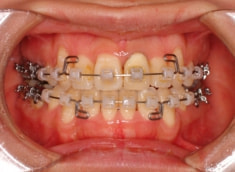

治療開始時

治療開始から約1年後